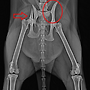

| 양측 골반다발성 골절+ 발목 골절(끊어짐) --교통사고 | 25.03.07 |